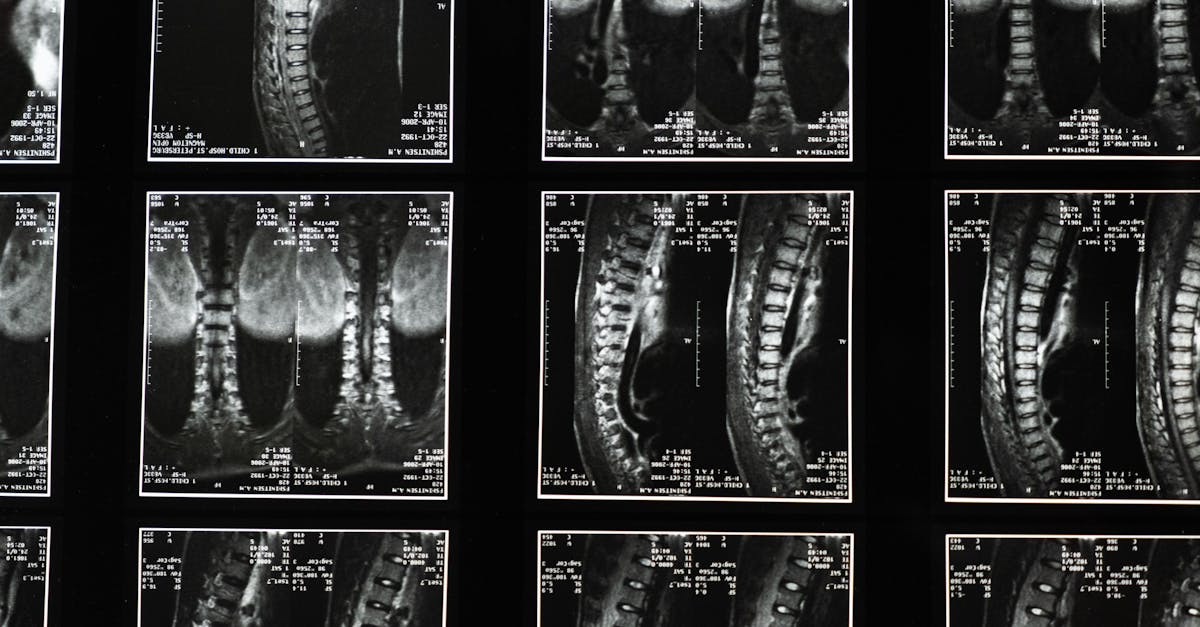

La ciática puede causar un dolor lumbar significativo.

y molestias, lo que lleva a muchos a buscar soluciones efectivas para aliviarlas. En Pulse Align, nos centramos en enfoques holísticos que fomentan la salud neuromuscular y promueven la mejora de la postura. Mediante técnicas sutiles, las personas que sufren afecciones como hernias discales o síndrome piriforme pueden descubrir formas naturales de aliviar sus síntomas. Este artículo profundiza en estas prácticas innovadoras, destacando la importancia del fortalecimiento del core y la corrección postural en el camino hacia la recuperación. La importancia del fortalecimiento del core Un aspecto fundamental para combatir la ciática de forma natural reside en fortalecer el core.

Los ejercicios de fortalecimiento del core, como las inclinaciones pélvicas y los ejercicios de tronco, desempeñan un papel vital en la estabilización de la columna vertebral y el soporte de la región lumbar. Al integrar estos ejercicios en su rutina, puede mejorar la simetría corporal y facilitar una mejor corrección postural. Explorando Técnicas Efectivas

En Pulse Align, los profesionales enfatizan la importancia de las técnicas adecuadas para levantar objetos y comprenden los matices de la estenosis espinal y su impacto en la movilidad general. Se recomienda utilizar una silla ergonómica durante las tareas diarias para minimizar el dolor lumbar, a la vez que se garantiza una postura óptima. Implementar posiciones adecuadas para dormir en caso de dolor de espalda también puede mejorar la recuperación y promover un sueño reparador. Abordando Problemas Subyacentes con una Recalibración Sutil El enfoque único de Pulse Align se centra en la recalibración del sistema nervioso para aliviar las molestias. Al abordar los problemas subyacentes que contribuyen a la ciática, las personas pueden experimentar un alivio duradero del dolor. Las técnicas que promueven el equilibrio natural pueden ayudar a las personas a recuperar la libertad de movimiento, permitiéndoles participar más plenamente en sus actividades diarias.